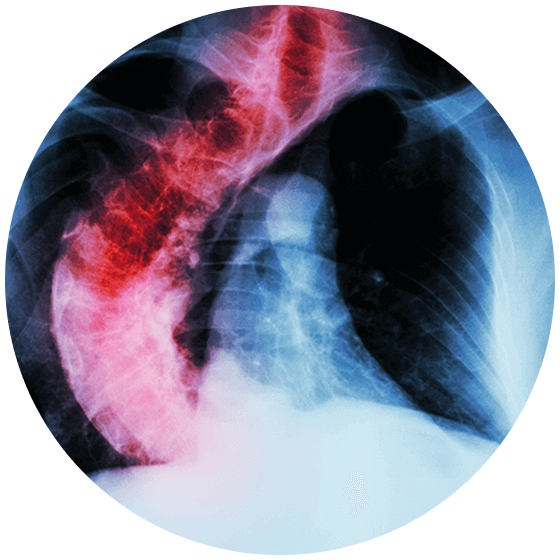

Management Strategies and Selection of Fusion Levels in Adult Spinal Deformities International Most Common Spinal Curvature Deformity Loss of sensation in the extremities. Idiopathic scoliosis is the most common spinal deformity in the world. Like other forms of scoliosis, idiopathic scoliosis affects the curvature of the spine. Lordosis is also known as swayback. Scoliosis, kyphosis, lordosis, and flatback. Scoliosis is a sideways curvature of the spine that most often is diagnosed in adolescents. The condition can create. Most Common Spinal Curvature Deformity.